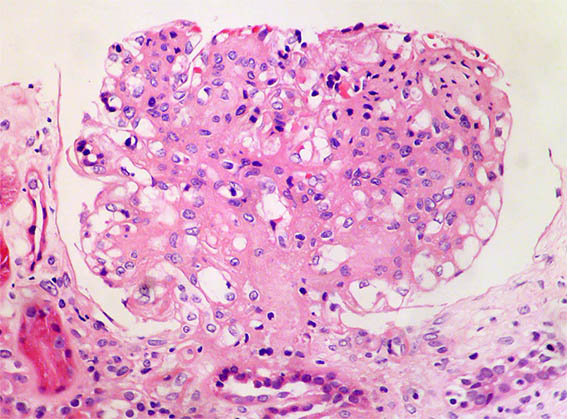

Figure 1. H&E, X100.

Figure 2. H&E, X400. Notable mesangial hypercellularity and glomerulomegaly.